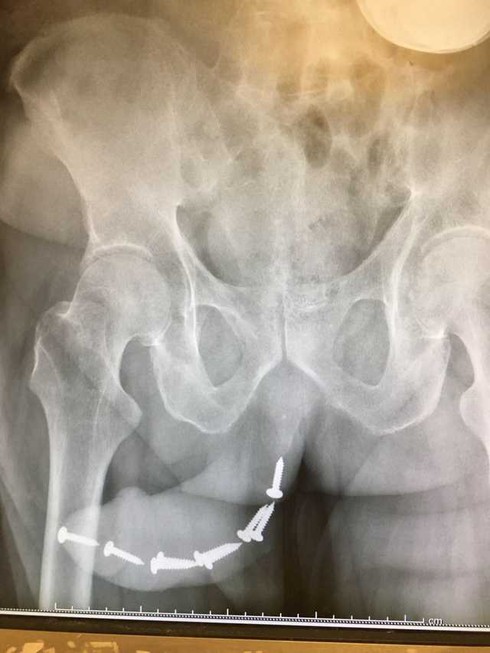

BS Dung cho biết, bệnh nhân ở Hà Nội đến phòng khám trong tình trạng tiểu buốt. Khám không có nấm nhưng chảy máu ở đầu dương vật, bác sĩ chỉ định bệnh nhân đi chụp phim thì phát hiện hàng loạt chiếc đinh cấy bên trong.

Quý ông cấy gần chục cái đinh vít vào dương vật.

Bệnh nhân được sang chuyên khoa Tiết niệu, gây mê và phẫu thuật gắp dị vật ra ngoài.